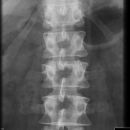

Sakroiliitis bei Bechterew